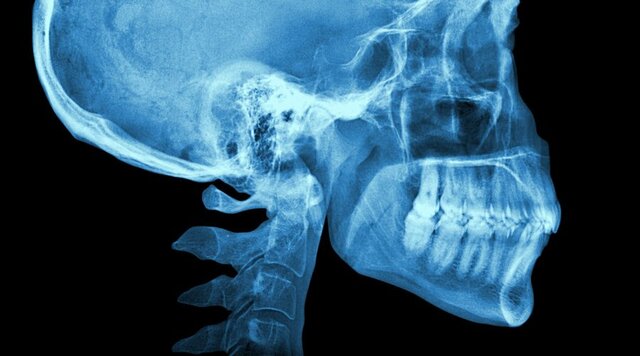

El descubrimiento llegó el 8 de noviembre de 1895. Mientras estudiaba el poder de penetración de los rayos catódicos, Röntgen observó que una placa de cartón cubierta de cristales de platino-cianuro de bario emitía una fluorescencia, que desaparecía al desconectar de la corriente. Dicha fluorescencia indicaba la presencia de un rayo que atravesaba la placa

Wihelm Conrad Roentgen, físico especializado en el campo de la electromagnética, logrando en 1901 el premio nobel de la física por su gran descubrimiento.